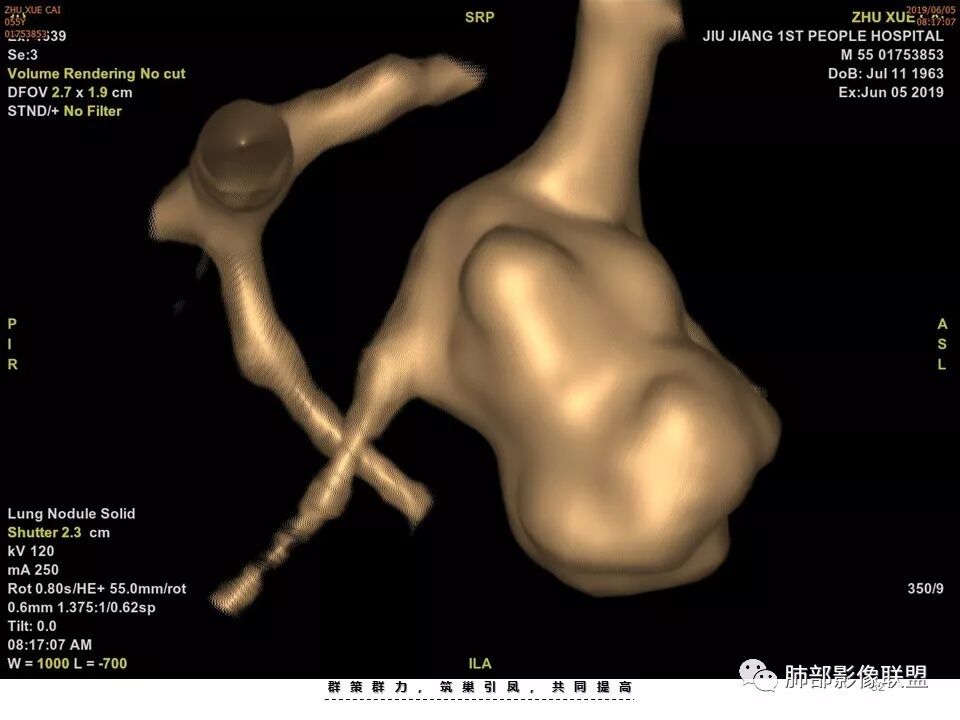

不是假象,是真的堵了,我工作站薄层做了气管曲面重建,仿真内窥镜也显示堵了

也咨询了病理科老师,肺软骨瘤来源于支气管透明软骨,理论上可以从黏膜下,突向支气管腔内生长,对支气管造成压迫性的阻塞。影像上和软骨瘤样错构瘤没法区分

肺软骨瘤好发年龄40~50 岁,男女发病无明显差异。多位于两肺外带,右肺多见。无明显临床症状,常在体检时偶然发现。若病灶发生于大支气管壁或病灶较大压迫支气管时(少见)可引起刺激性咳嗽、咳痰等症状。

典型CT特征包括:(1)圆形或椭圆形边界清楚的病灶。(2)大小1~4cm,有轻微分叶改变。(3)较均匀的软组织影,多伴有钙化。(4)无毛刺,卫星灶及肺门或纵隔淋巴结肿大。(5)CT增强扫描无强化或轻度强化,其强化可能与软骨瘤间质中的薄壁血管或周围慢性炎症反应有关。

鉴别诊断,主要是错构瘤。错构瘤是肺内最常见的良性肿瘤。错构瘤内常见“爆米花”样钙化,而软骨瘤钙化则多呈点状或环状钙化。病灶内脂肪密度影是错构瘤的特异性征象,而软骨瘤内无脂肪成分。此外尚需要与肉芽肿性炎、硬化性肺细胞瘤、肺癌、转移等鉴别。